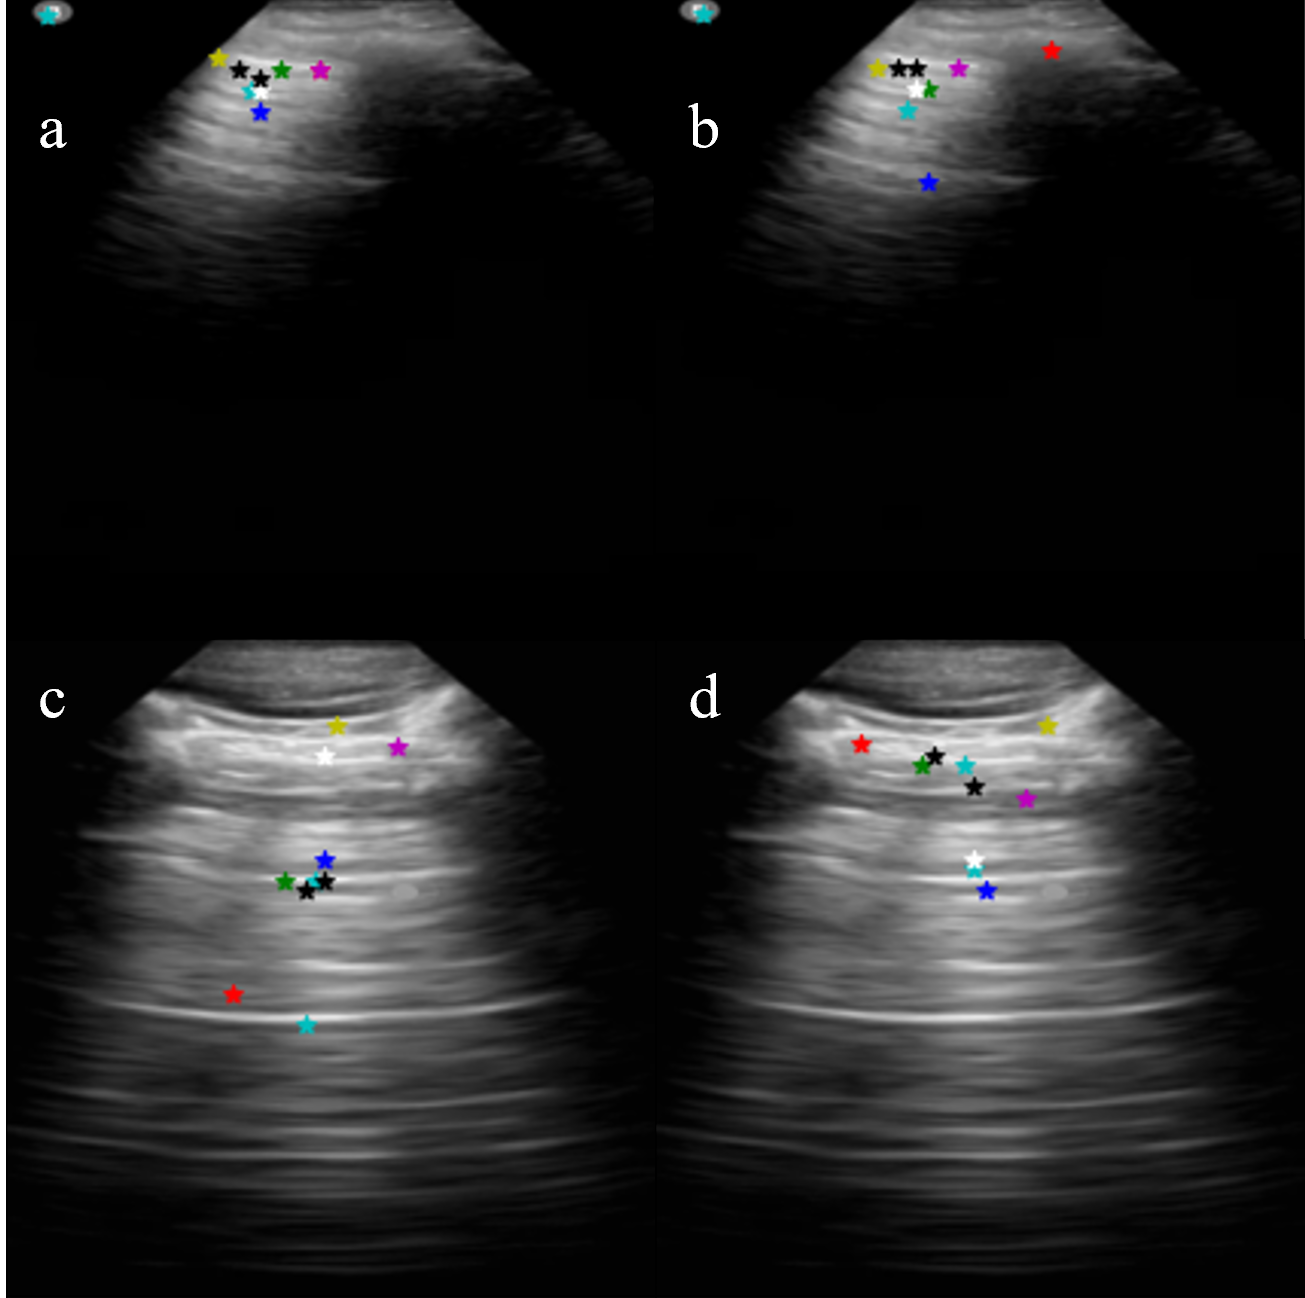

We compare the evaluation results obtained by preprocessing raw LUS frames into 101010 channels of varying wavelength acoustic feature fusion maps (formed by DGA and RT-FPM) and 101010 channels of grayscale images with varying levels of normalization, i.e, normalising the raw LUS frames by assuming a standard deviation (σ𝜎\sigma) and a mean (μ𝜇\mu) and clipping resultant pixel values to the range 0 and 1. For the latter, normalization with standard deviation (σ𝜎\sigma) of 0.5 and mean (μ𝜇\mu) varied linearly between 0.30.30.3 and 0.70.70.7 with respect to the index of the channel are employed to form 101010 input channels for the FF-CNN. The results for this ablation study, as shown in Fig. 5, shows that the normalization process filters out irrelevant features of the LUS images and results are comparable with that of acoustic feature fusion. Acoustic feature fusion (DGA and RT-FPM) is closer to the desired landmarks (pleura in this case).

Refer to caption

Figure 5: (a, c) With normalized images by linearly varying (μ𝜇\mu, σ𝜎\sigma) parameters to form 10 input channels, (b, d) With acoustic feature fusion images by 10 varying wavelengths. The acoustic feature fusion (DGA and RT-FPM) is more closer to the desired landmarks (pleura in this case).